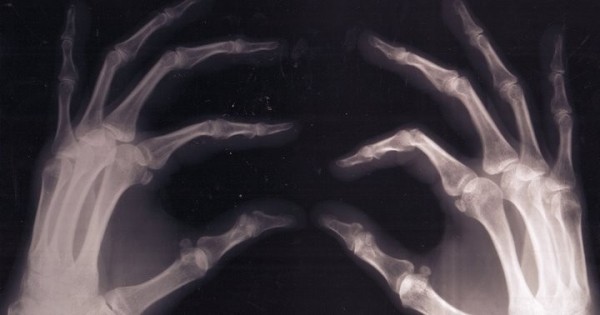

С возрастом или из-за неправильного образа жизни кости человека могут стать хрупкими, появляются серьезные проблемы со здоровьем. Если питаться несбалансированно, с частыми перекусами на ходу, возможен дефицит витаминов и минеральных веществ. В частности, опасна нехватка кальция и витамина D, ведь это своего рода строительный материал для костей.

Фото: из открытых источников (иллюстративное)